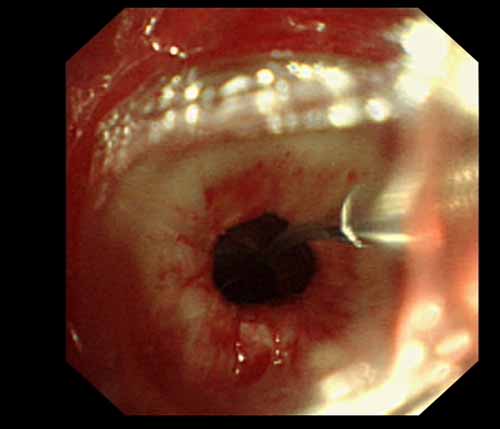

患者李某某,女,45歲,因氣管插管咳嗽、喘憋10天入院。頸部CT檢查示聲門下約20mm處氣管明顯狹窄,狹窄段長約26mm,最窄處直徑約4.4mm。支氣管鏡檢查見聲門下約2cm氣管呈漏斗狀縮窄,直徑約4-5mm,支氣管鏡無法通過。經(jīng)科室討論,決定行電子支氣管鏡下氣管球囊擴(kuò)張治療。與患者及家屬充分溝通并經(jīng)三方見證談話簽署知情同意書后,在患者持續(xù)吸氧、局麻下,科主任于世倫主任醫(yī)師帶領(lǐng)治療小組為患者實(shí)行電子支氣管鏡下氣管球囊擴(kuò)張術(shù)。手術(shù)過程順利,出血量很少,術(shù)后患者呼吸困難癥狀即可明顯緩解。10天后行二次擴(kuò)張,患者日常活動(dòng)無明顯喘憋,二次術(shù)后5天出院。

術(shù)前聲門下的漏斗樣狹窄口

術(shù)中球囊擴(kuò)張